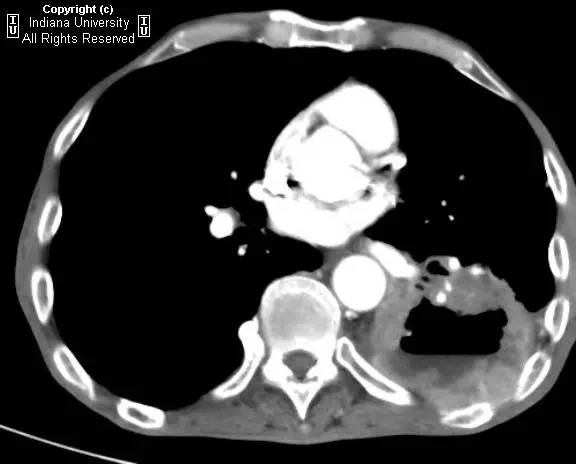

【病史】男性,咳嗽,体重减轻。

胸片示肺内高度膨胀性病变,膈肌扁平。左后胸部可见较大卵圆形不透亮区并液平面。CT示左肺下叶近后胸壁较大厚壁肿块并部分空洞形成,实性部分不均质强化。右肺下叶可见分叶状结节。左前下少量气胸。

【诊断】鳞状细胞肺癌并后部阻塞性肺炎